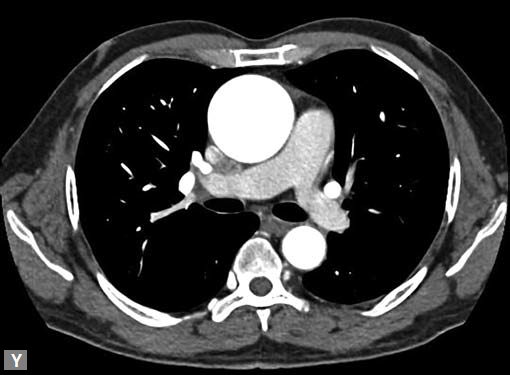

Filling defects (Figs 16A and B) may be seen in main

pulmonary artery (MPA), left pulmonary artery (LPA) and

right pulmonary artery (RPA), interlobar artery, segmental

divisions (Figs 17A and B). On occasions, detection in distal

parts of segmental divisions is difficult. This can be further

confounded by motion artifacts, non- or minimally opacified

accompanying pulmonary veins.